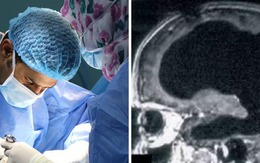

Một người đàn ông Pháp sống một cuộc sống tương đối bình thường, khỏe mạnh - mặc dù bị tổn thương 90% não bộ - đang khiến các nhà khoa học phải suy nghĩ lại về điều gì từ góc độ sinh học khiến chúng ta có ý thức.

Kinh ngạc phát hiện người đàn ông gần như không có não, trong khoang sọ chỉ toàn chất lỏng vẫn sống bình thường: Nguyên nhân vì sao?

24/04/2024 22:40

Bệnh nhân 44 tuổi có đầy đủ nhận thức như bao người dù mang bộ não khác thường.